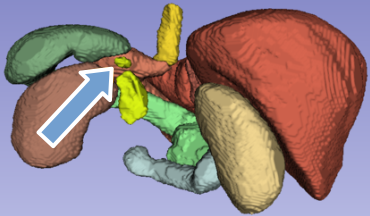

Figure 1: Shall we label the gray spot indicated by the blue arrow adrenal gland? (a) scan slice, (b) ground truth (with adrenal gland label removed) 3D segmentation around the slice, (c) all baseline segmentation wrongly segmented the spot as gland, and (d) AIC-Net gives correct segmentation.

So, what causes existing segmentation models to find it difficult to recognize anatomical features, which humans can grasp from just a handful of examples, despite being trained on hundreds of thousands of instances? AI-driven segmentation models are trained to detect organs solely from CT/MRI scans (Çiçek et al. 2016; Chen et al. 2018; Hatamizadeh et al. 2021). Ideally, a robust model should extract both local and global features, using global features to distinguish similar-looking local features. However, we often observe that when relying solely on the scan as input, these models tend to overlook learning global patterns. For example, in the scan slice shown in Figure 1(a), base on local patterns it is difficult to tell if the gray spot, as indicated by the blue arrow, should be segmented as left adrenal gland or not. It is positioned directly above the right kidney, where the gland typically appears, and has similar intensities to the average adrenal gland. All baseline models we tested wrongly segmented it as part of the left adrenal gland, as shown in Figure 1(c). However, this results in a separated component of the gland, clearly violating the anatomy. Our proposed method can give correct segmentation.